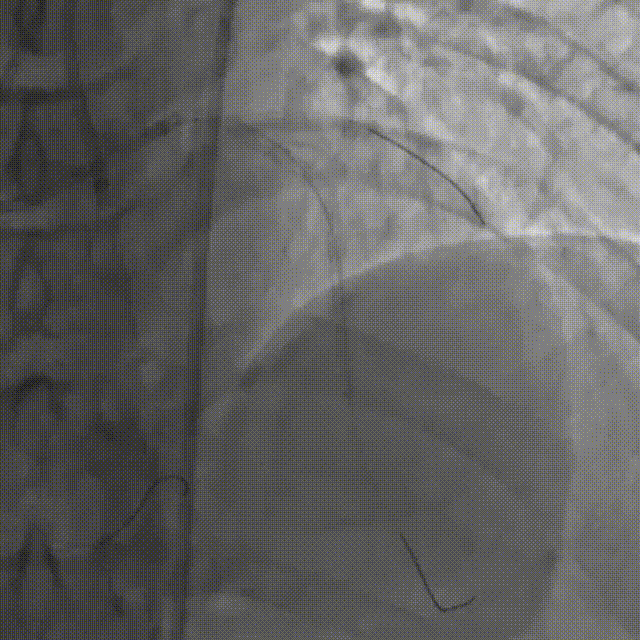

直接尝试逆向,RCA中段3.0*10切割后,使用Finecross150+SUOH03通过心外膜逆向进入LAD,FC轻松跟进。

使用P200导丝攻击远端纤维帽前进困难,更换G3进入LAD近段内膜下,直接使用Telescope™导引延长导管辅助下AGT技术,r-CART后G3顺利进入Telescope™导引延长导管。

直接使用G3导丝rendezvous,球囊扩张后行IVUS检查确定血管直径及支架落脚点。